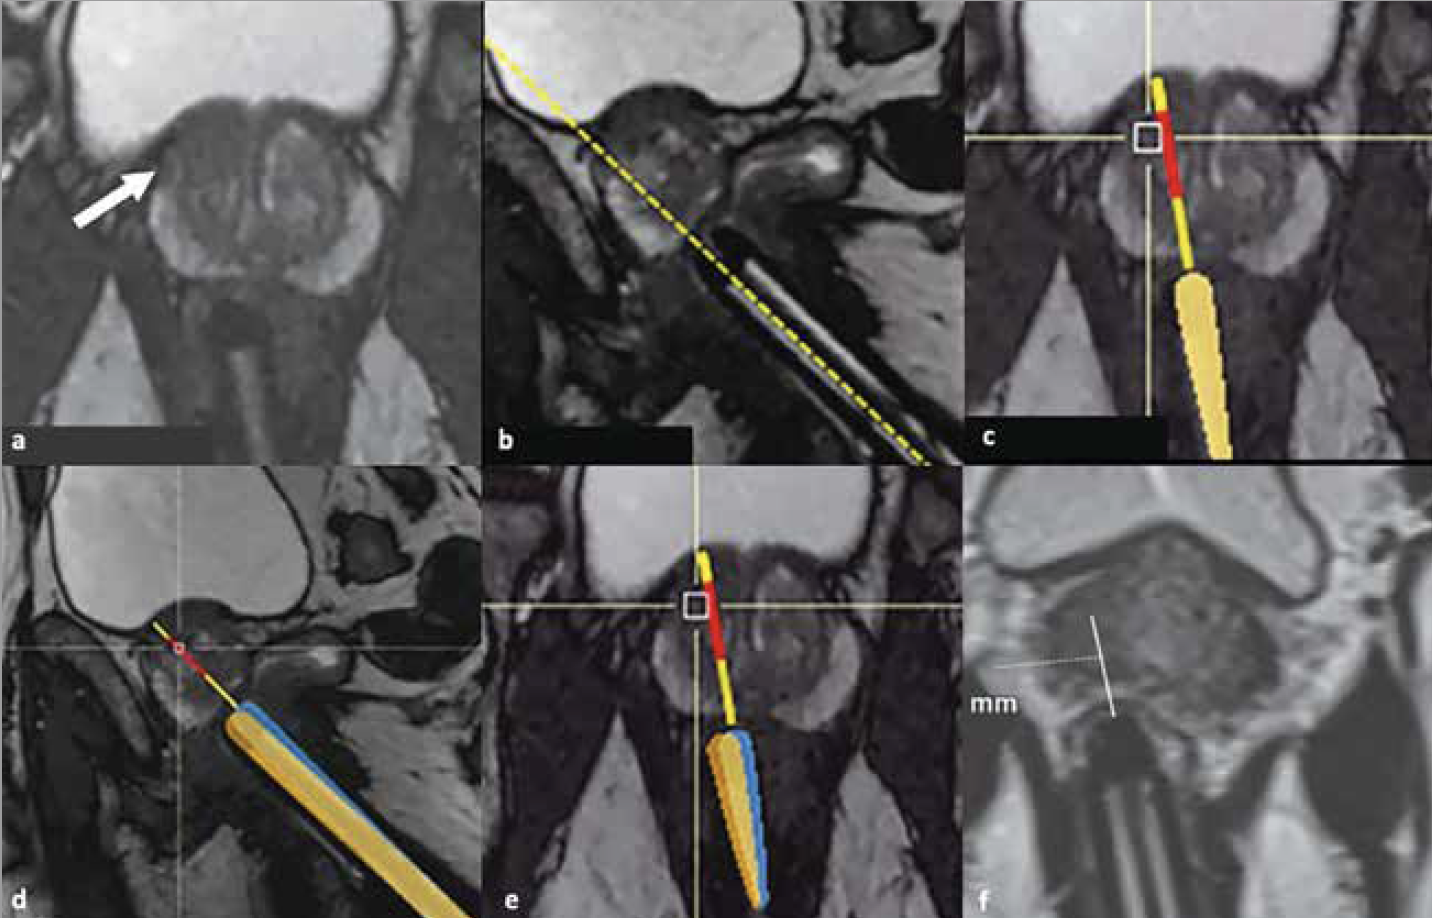

Elles sont réalisées à l’aide d’un robot IRM compatible, disposé entre les jambes du patient, installé en décubitus ventral. Des séries axiales et sagittales T2 rapides sont acquises et transférées à un logiciel permettant, après avoir repéré la lésion cible, d’aligner le guide avec la cible puis d’effectuer les biopsies ciblées (Fig. 5).

Figure 5 – Biopsies ciblées sous guidage IRM par voie transrectale (25).

Anomalie focale de la ZT antérieure droite (a, flèche) chez un patient de 67 ans avec un PSA à 8,1 ng/ml. Après mise en place du robot, ciblage de l’anomalie sous guidage IRM sur des séquences rapides axiales et sagittales (b, c) avant prélèvement qui permettent d’ajuster la précision du ciblage avant prélèvement (d, e). Une fois la mesure de la distance jusqu’à la cible effectuée (f), la biopsie peut être réalisée.